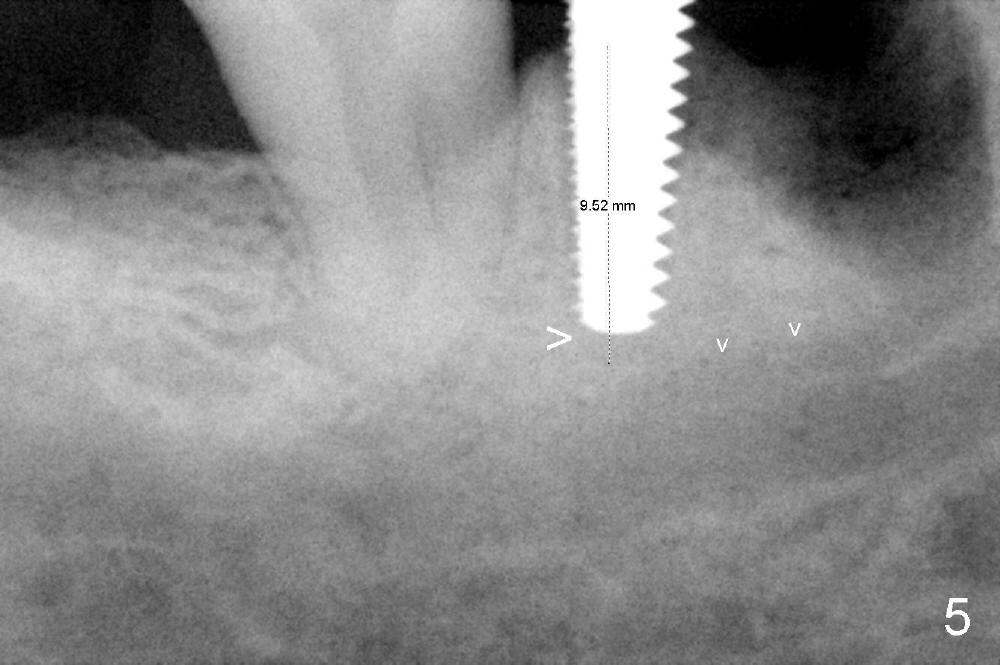

As to where to place an implant, we try to engage the largest tap (8 mm in diameter) into the mesial socket without binding. The buccal plate of the mesial socket is missing. It is risky to extend osteotomy in the mesial socket. Besides, the septum (Fig. 4 S) is not as tall as the distal socket (D). It appears that the distal socket is the safest place to place an implant. Furthermore, no drill is used for distal osteotomy. Instead two osteotomes (3.5x15 and 4x15 mm tapered osteotomes) are used to expand the distal socket with intention to push the septum mesially. Since the bone density is high, the osteotomes seem not to work as effectively as expected. Then a 4.5x17 mm tap is placed at the depth ~ 14 mm with stability (Fig.5). Finally a 5x14 mm tissue-level implant is placed with insertion torque >60 Ncm (Fig.6). Allograft is placed in the mesial socket and buccal aspect of the distal socket, followed by insertion of collagen plug and membrane (Fig.7). After insertion of an abutment (Fig.8 (taken 6 days postop) *), perio dressing (P) is applied to cover the wound. There is no postop paresthesia.